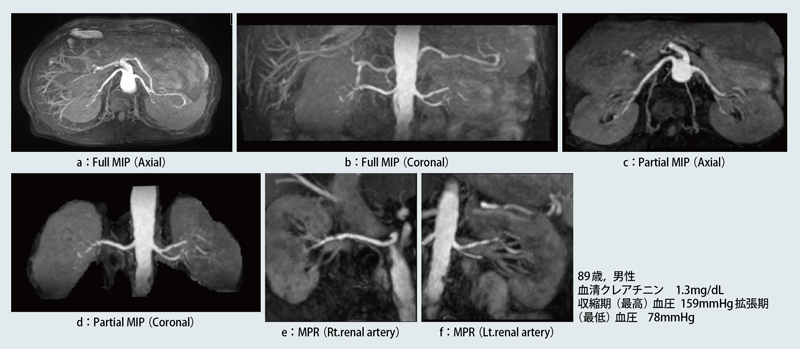

症例1は,89歳,男性で,収縮期/拡張期の血圧が159mmHg/78mmHg,血清クレアチニン値が1.3mg/dLとやや高値のため,腎血管性高血圧症を疑い,MRAが施行された。経験的に高齢者では,動脈硬化や心拍出量の低下により末梢動脈の描出が劣るので,本症例ではTI 2200msに設定した。Full MIPでは,IR pulseを3回印加しているので,IVCはほぼ完全に抑制されている (図3 a,b)。

図3 症例1:腎血管性高血圧症疑い